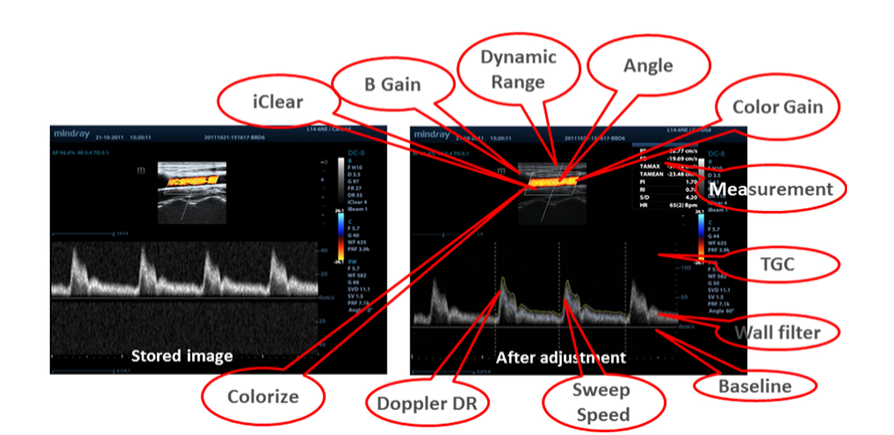

Datos en bruto

Permite una flexibilidad óptima para el posprocesamiento de las imágenes almacenadas, incluidos el ajuste de parámetros, y la adición de comentarios y mediciones, lo que permite una productividad máxima durante el escaneo.